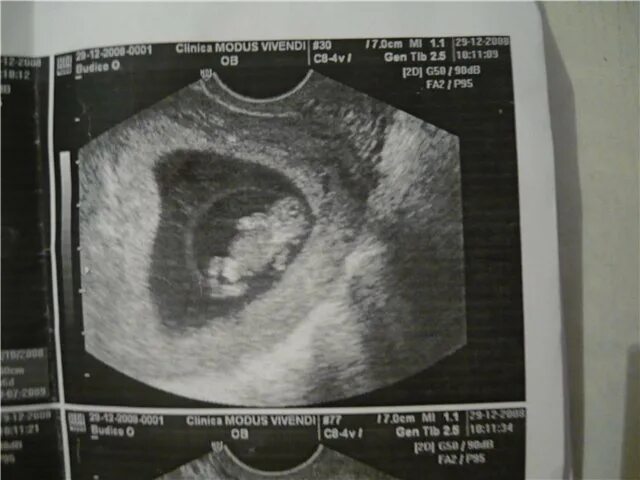

Эмбрион 7 дня форум